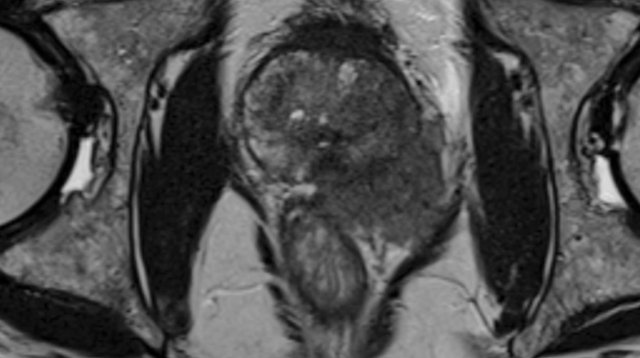

Prostate Cancer - PI-RADS v2.1

Prostate Anatomy